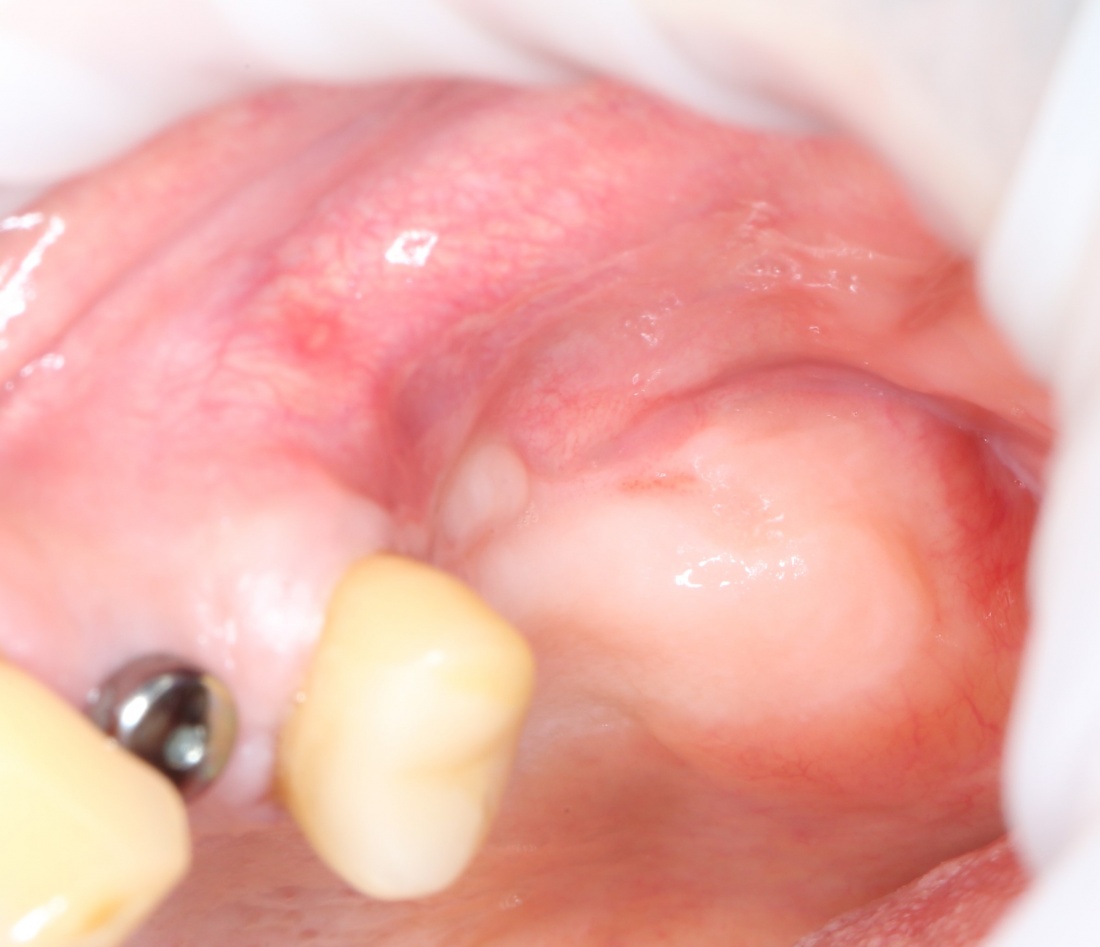

Устанавливаем формирователи десневой манжеты. Сегодня я называю эту процедуру не менее важной, чем любой другой этап имплантологического лечения:

И швы. Просто швы. Никаких дополнительных процедур.

Если честно, то сейчас бы я использовал другой шовный материал и другой тип швов. Одно неизменно, — и я об этом много раз говорил, — самая широкая часть формирователя десны должна находиться на уровне десны. Так, чтобы эффективно отрабатывать т. н. «биологическую ширину».